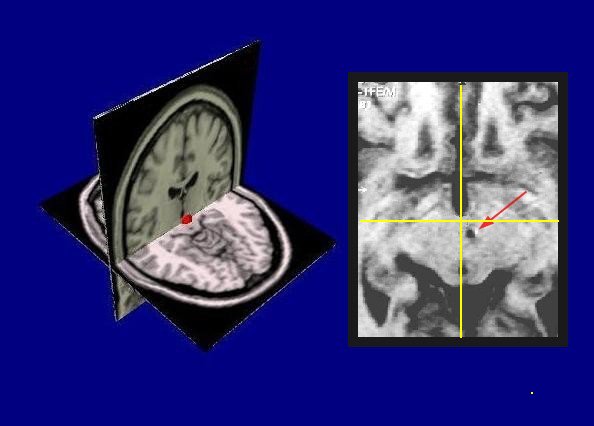

posteromedial hypothalamus

Angelo Franzini